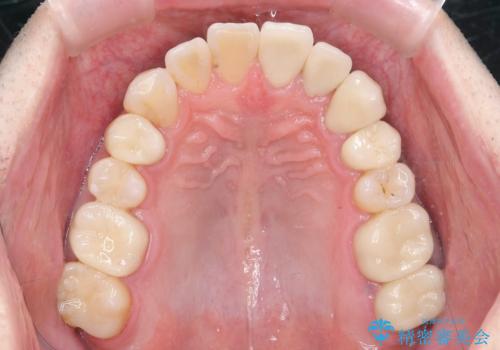

全ての銀歯を外すメタルフリー治療 + 歯並びをきれいにする矯正治療

放置すると大きくなりそうな虫歯をまず治療、矯正治療を行ったのち、全ての銀歯を除去しセラミック治療を行う治療計画としました。

長年の悩みであった虫歯や、噛み合わせ、歯並びの問題が解決でき喜んでいただくことができました。